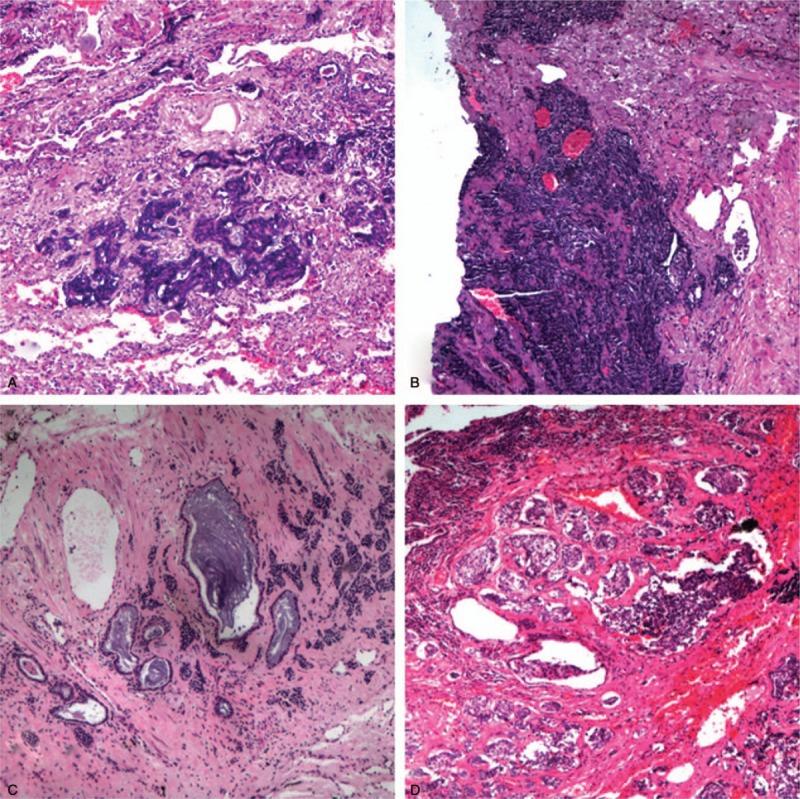

Case 1: A 57-year-old female had chest pain, and computer tomography (CT) examination prompted a mass shadow of left lung lower lobe. Case 2: A 64-year-old female had cough and expectoration for more than 1 month. CT examination showed: a lump with diameter of about 2.5 cm and irregular edge was in right lung upper lobe, being largely possibly lung cancer. Case 3: A 54-year-old male, CT examination accidentally found a long strip-shaped nodule in left lung oblique fissure when checkup's, and he had no fever, cough, expectoration, chest tightness, or chest pain. Case 4: A 61-year-old male, checkup's CT examination accidentally found a nodule, fibrosis, bronchiectasis, and secondary infection in the left lower lobe. Combined with pathological morphology and immunohistochemistry, cases 1 and 3 were diagnosed as DIPNECH with multiple carcinoid tumorlet formation and chronic inflammation and bronchiectasis, case 2 was diagnosed as an adenocarcinoma with DIPNECH and multiple carcinoid tumorlet formation, case 4 was diagnosed as an adenocarcinoma with DIPNECH and multiple carcinoid tumorlet formation and chronic inflammation and bronchiectasis.

DIPNECH is often found accidentally in a surgical specimen, is easily missed, and needs careful observation. Immunohistochemistry is necessary to make this diagnosis.